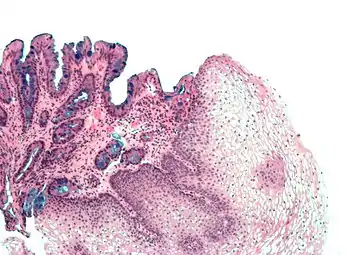

[Micrograph] of normal stratified squamous epithelium and the metaplasic epithelium of Barrett's esophagus (left of image). Alcian blue stain.